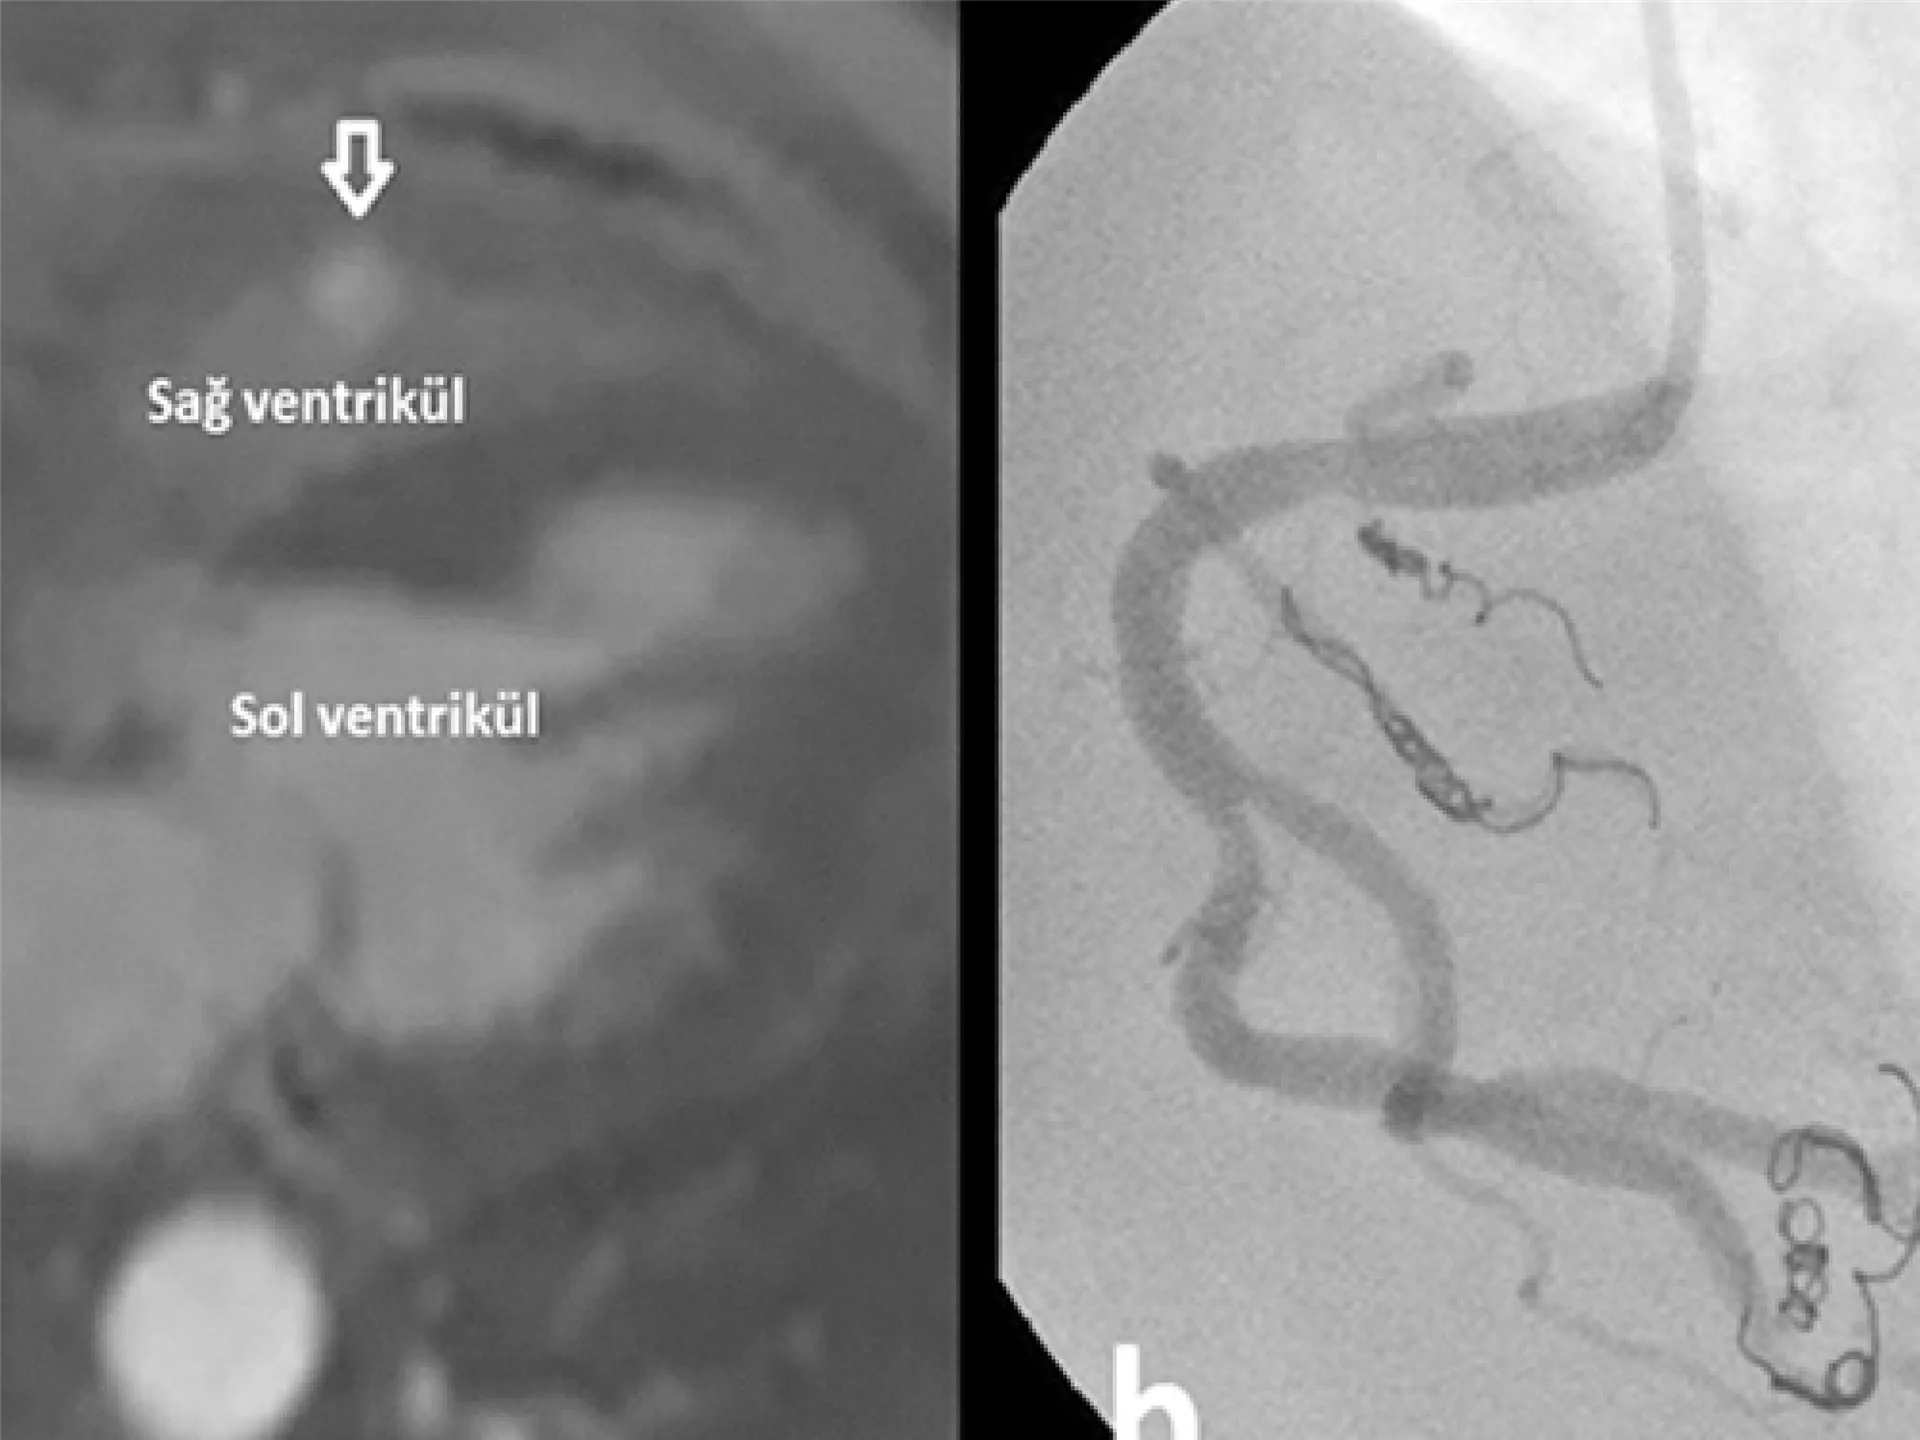

Coronary And Peripheral Vascular Fistula And Embolization Treatments

Coronary and peripheral vascular fistulas are abnormal connections between blood ...